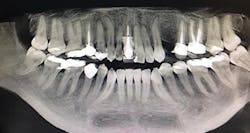

Figure 1a: Pre-op panorex

Figure 5: Post-op panorex

A 32-year-old male presented with a congenitally missing lateral, No. 10. The buccal-lingual dimensions were sufficient for standard implant placement, but the mesial-distal dimensions were 4.56 mm (figures 1a and 1b). The patient had a failing Maryland bridge, both functionally and esthetically (figure 2). He was always told that implants were not an option for him unless he underwent significant orthodontic treatment, and even then, nothing was guaranteed.

By selecting a 2.4 mm Anew implant (Dentatus), we were able to preserve sufficient bone between implant and tooth (1.5 mm), allowing for gingiva, a natural emergence profile, and maintaining the papilla in this highly esthetic area. Gingival recontouring was performed with a diode laser (Epic, Biolase). We had the lab fabricate a surgical guide and an immediate screw-retained provisional restoration for flapless implant placement (figures 3 and 4).